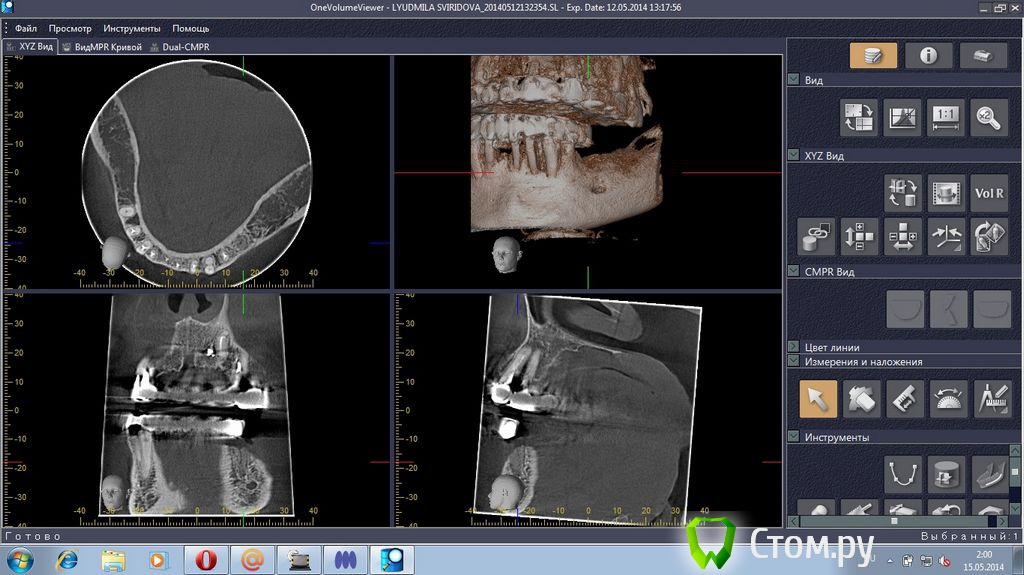

stradalitca Опубликовано 18 мая, 2014 Поделиться Опубликовано 18 мая, 2014 Здравствуйте! у меня проблема такая. за последние 4 года мне удалили нижний центральный зубик (киста была), пролечили каналы в нижних зубах. Поставили мост с металлокерамики. Он простоял некоторое время, а потом( год-два) просто стал качаться. Его раза три сажали заново на цемент( прошлым летом). в итоге, пошла в другую клинику. Мост ещё раз сняли( он держался на честном слове). Оказалось, что пятёрка снизу слева пробита вкладкой. Зуб удалили. На сдедующий день обточили ещё зубы некоторые и сняли слепок под новые пару вкладок. через неделю поставили на цемент( сразу на цемент, без времянки)НОВЫЙ мост. Это было в конце декабря. Через две недели десну разнесло и прищлось резать, выпускать гной( надрез примерно под тройкой слева). Сейчас опять явный свищ примерно под 3-4 нижними слева.Сделали рентген - оказалось, что тройка имеет два корня и она пробита вкладкой. Теперь даже не знаю что делать. Просто резать десну и опять чистить? Врач говорит, что надо снять мост и удалить тройку. Другой врач говорит, что тройку может и можно спасти, надо снять мост, убрать вкладку и смотреть, что с тройкой. На прошлой неделе сделала объёмный рентген. Сама неделю копалась в программе, разглядывя свою нижнюю челюсть. мне показалось, что там маячит какой-то остаток корня шестёрки слева( мне его сто лет назад удаляли). Пожалуйста, подскажите, что делать? какие перспективы и варианты есть на мои нижние зубы?Заранее большое спасибо за все ваши ответы и мнения.Скриншоты с программы 3D прилагаю.или может надо мост снять, выдернуть тройку слева и поставить металлопластмассу?( верхние зубы тоже штук 8 слитно металлокерамика, ставили первый паз отдновременнно нижние и верхние) Ссылка на комментарий

stradalitca Опубликовано 20 мая, 2014 Автор Поделиться Опубликовано 20 мая, 2014 (изменено) Добрый вечер! Я тут ещё глянула как установлен штифт на четвёрке снизу справа. Вот фото в проекциях. Неужели зуб тоже пробит штифтом? или пойдёт ? и я зря переживаю. Изменено 20 мая, 2014 пользователем stradalitca Ссылка на комментарий